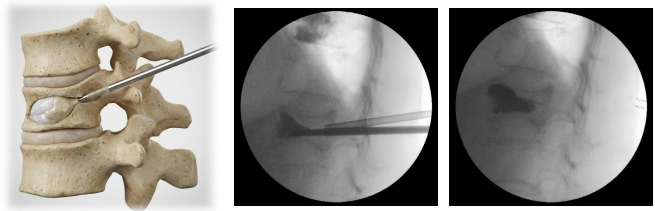

経皮的椎体形成術は、骨折した椎骨をセメントで固めて痛みをとる手術です。全身麻酔が必要ですが、皮膚切開は左右に約5mmと小さく、筋肉のダメージもごく僅かです。透視(レントゲン撮影)を見ながら、専用のニードル(細い筒)を骨に差し込み、バルーンを膨らませて潰れた骨を形成して空洞を作り、この空洞にセメントをいれて安定化させます。手術は30~40分ほどで、出血はごく少量です。

背中の左右に5mmの皮膚切開をし、ニードルを椎体に刺入します

バルーンを膨らませて、セメントを入れるスペースを作ります

セメントを注入します。セメントが固まったら、ニードルを抜き、創部を閉じて終了です